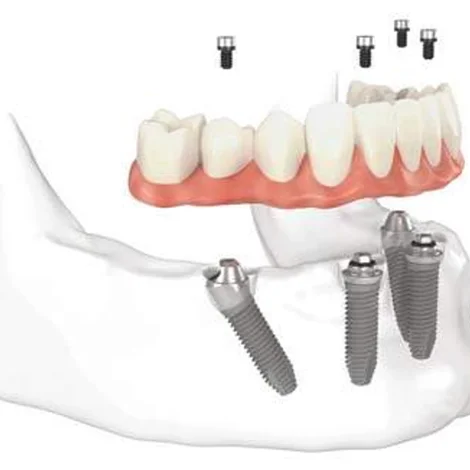

Implantologia Guidata: chirurgia mini-invasiva di alta precisione.